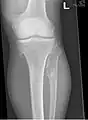

It is characterized by the growth of cartilage-capped benign bone tumours around areas of active bone growth, particularly the metaphysis of the long bones. Typically five or six exostoses are found in upper and lower limbs. Image depicts adult regrowth after knee replacement.

The diagnosis of HMO is based upon establishing an accurate correlation between the above-mentioned clinical features and the characteristic radiographic features. Family history can provide an important clue to the diagnosis. This is supplemented by testing for the two genes in which pathogenic variants are known to cause HMO namely EXT1 and EXT2. A combination of sequence analysis and deletion analysis of the entire coding regions of both EXT1 and EXT2 detects pathogenic variants in 70–95% of affected individuals.[3][5] The hallmark of radiographic diagnosis is the presence of osteochondromas at the metaphyseal ends of long bones in which the cortex and medulla of the osteochondroma represent a continuous extension of the host bone. This is readily demonstrable in radiographs of the knees.[3][1]

multiple osteochondromas around the knee- CT of osteochondroma in MO